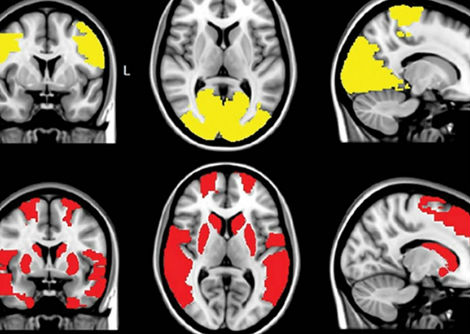

نسيج دماغ بشري مُستأصل، مُجمد بعد 100 مللي ثانية من التحفيز، يُظهر بنيةً داخلية. مقياس الشريط = 100 نانومتر.